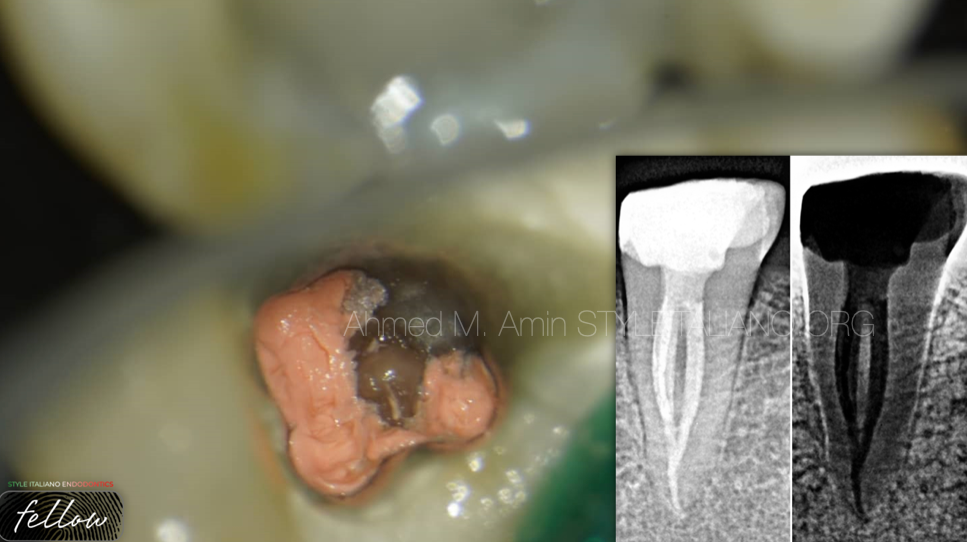

当根管再治疗遇到髓室底大穿孔

髓腔穿孔(通常是髓室底穿孔)是我们开始进行根管再治疗时可能面对的需要解决的问题之一。当我们谈到控制和解决这类问题的步骤时,有很多困惑和问题。在本文中,我将逐步描述所有步骤,使此...